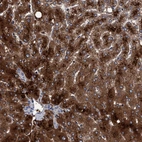

Immunohistochemical staining of human liver shows strong cytoplasmic positivity in hepatocytes.